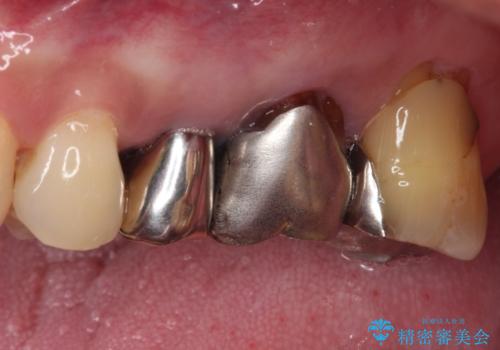

より審美的で、より機能的に優れた治療をご希望とのことであったので、ジルコニアカスタムアバットメントを用いたインプラント治療を行うこととしました。

ジルコニアカスタムアバットメントは、歯肉ラインに金属が見えにくいというだけでなく、クラウンを装着する土台の形が天然歯と近い形態となるため、清掃性が高く歯肉が腫れにくいというメリットがあります。

インプラントは、骨との生着能が比較的高いとさせるSLAタイプを使用しました。